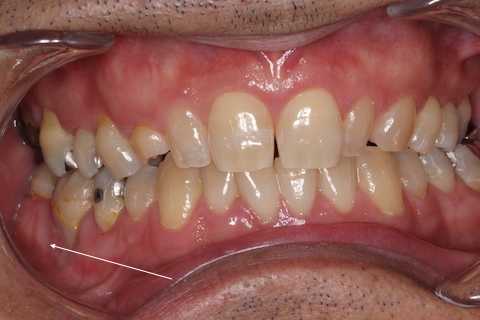

残根上のCR8 2025.10.28